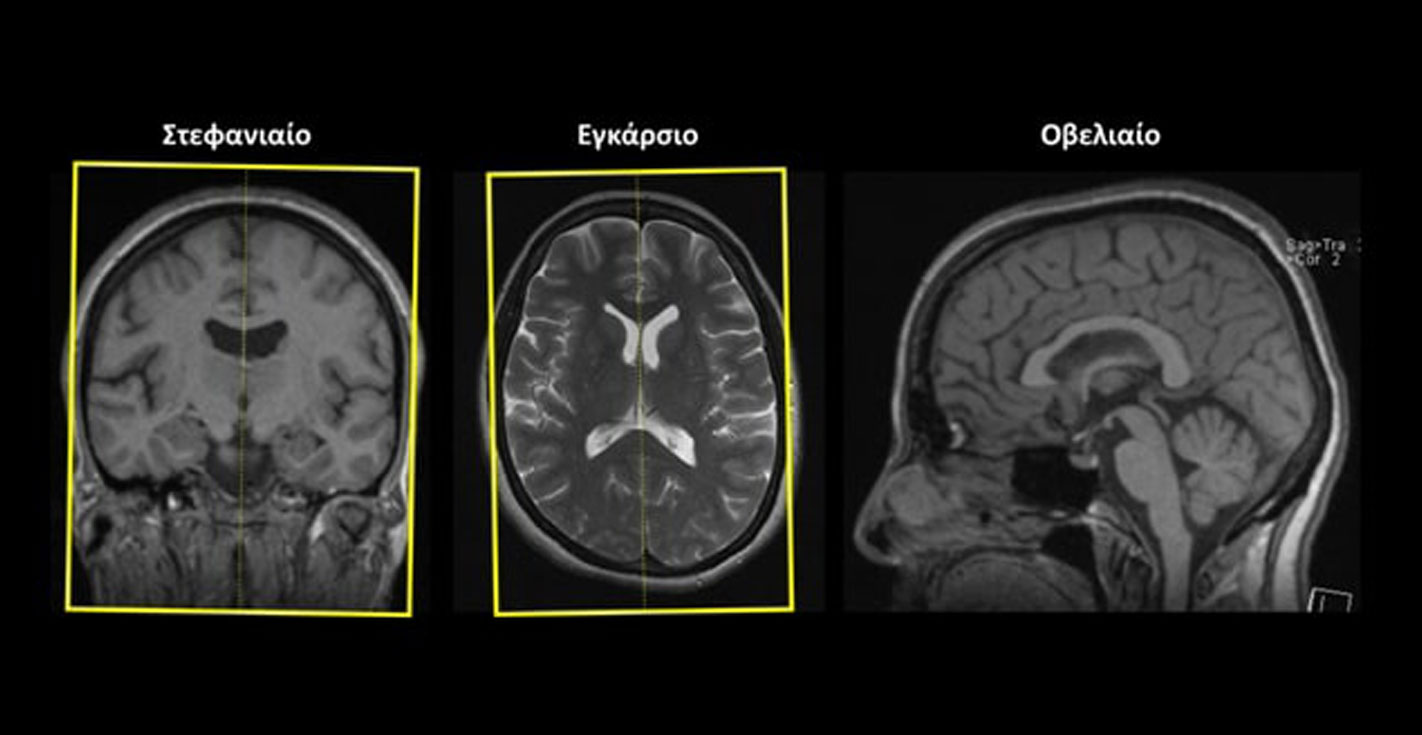

Εγκάρσιο (Axial/Transversal): οι εγκάρσιες τομές σχεδιάζονται παράλληλα με το πρόσθιο (γόνυ) και το οπίσθιο (σπληνίο) κέρας του μεσολοβίουστο οβελιαίο επίπεδο και κάθετα στη μέση γραμμή του εγκεφάλου στο στεφανιαίο επίπεδο. Οι τομές πρέπει να περιλαμβάνουν ολόκληρο τον εγκέφαλο έως και την παρεγκεφαλίδα (κάτω).

Οβελιαίο (Sagittal):οι οβελιαίες τομές σχεδιάζονται παράλληλα με τη μέση γραμμή του εγκεφάλου τόσο στο στεφανιαίο όσο και στο εγκάρσιο επίπεδο. Οι τομές πρέπει να περιλαμβάνουν ολόκληρο τον εγκέφαλο.

Στεφανιαίο (Coronal): οι στεφανιαίες τομές σχεδιάζονται κάθετα με τη νοητή γραμμή που ενώνει το πρόσθιο (γόνυ) και το οπίσθιο (σπληνίο) κέρας του μεσολοβίου στο οβελιαίο επίπεδο και κάθετα στη μέση γραμμή του εγκεφάλου στο εγκάρσιο επίπεδο. Οι τομές πρέπει να περιλαμβάνουν ολόκληρο τον εγκέφαλο.